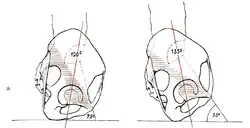

В строении таза у взрослого человека чётко прослеживаются половые особенности и отличия. Особенности в анатомии женского таза проявляются в первую очередь его большим размером, большим объёмом и увеличенной нижней апертурой. Данные анатомические отличия связаны с функцией — таз у женщин является вместилищем развивающегося плода, который впоследствии во время родов проходит через нижнюю апертуру таза. Таким образом таз у женщины шире и ниже, а все его размеры больше, чем у мужчины. Помимо этого кости женского таза тоньше, чем у мужского. Крестец у мужчин вогнутый и более узкий, а его мыс выражено выдаётся вперед. У женщин крестец, наоборот уплощён и более широкий, мыс выражен меньше и не так выдаётся вперёд, благодаря чему верхняя апертура женского таза является более округлой, чем у мужского. Подлобковый угол, под которым происходит соединение нижних ветвей лобковых костей, у мужчин является острым, а у женщин он приближается к прямому или даже тупому углу, его вершина является более закругленной, а ограничивающие его нижние ветви лобковых костей образуют лобковую дугу (аrcus pubis). Лобковый симфиз также характеризуется наиболее выраженными половыми особенностями строения. У женщин он короче по высоте, межлобковый диск более толстый, чем у мужчин. Небольшие движения у женщин в лобковом симфизе возможны во время процесса родовой деятельности, в то время как у мужчин движения в лобковом симфизе отсутствуют.

| Подлобковый угол | 70-75° | 90-100° |

| Угол наклона таза | 50-55° | 55-75° |

Угол наклона таза

(на рисунке = 54°)